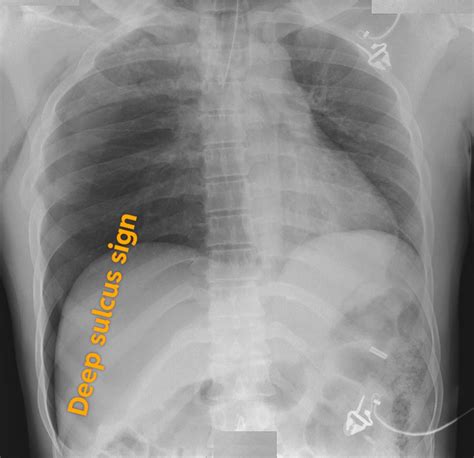

In the high-stakes environment of emergency medicine and diagnostic radiology, identifying subtle signs of pathology can mean the difference between life and death. One such critical indicator often encountered during the evaluation of portable chest radiographs is the Deep Sulcus Sign. This radiologic finding is a key marker for a pneumothorax—a condition where air leaks into the space between the lung and the chest wall—specifically when the patient is in a supine position. Because supine patients cannot have air rise to the apex of the lung as it would in an upright individual, the air instead collects anteriorly and inferiorly, creating a distinct visual marker that clinicians must be trained to recognize instantly.

The Deep Sulcus Sign is characterized by an abnormally deep and lucent (dark) costophrenic angle on a supine chest X-ray. Under normal circumstances, the costophrenic angle—the sharp point where the diaphragm meets the ribs—should be relatively shallow. When a pneumothorax occurs in a supine patient, the free air tracks to the most non-dependent part of the pleural space, which, in this position, is the anterior and lateral costophrenic sulcus.

This accumulation of air causes the costophrenic angle to appear hyperlucent and deeper than usual, often extending further inferiorly than the contralateral side. Recognizing this sign is paramount because, in supine radiography, standard signs of pneumothorax—such as the visualization of a visceral pleural line—are frequently absent or obscured, leading to a high rate of missed diagnoses.